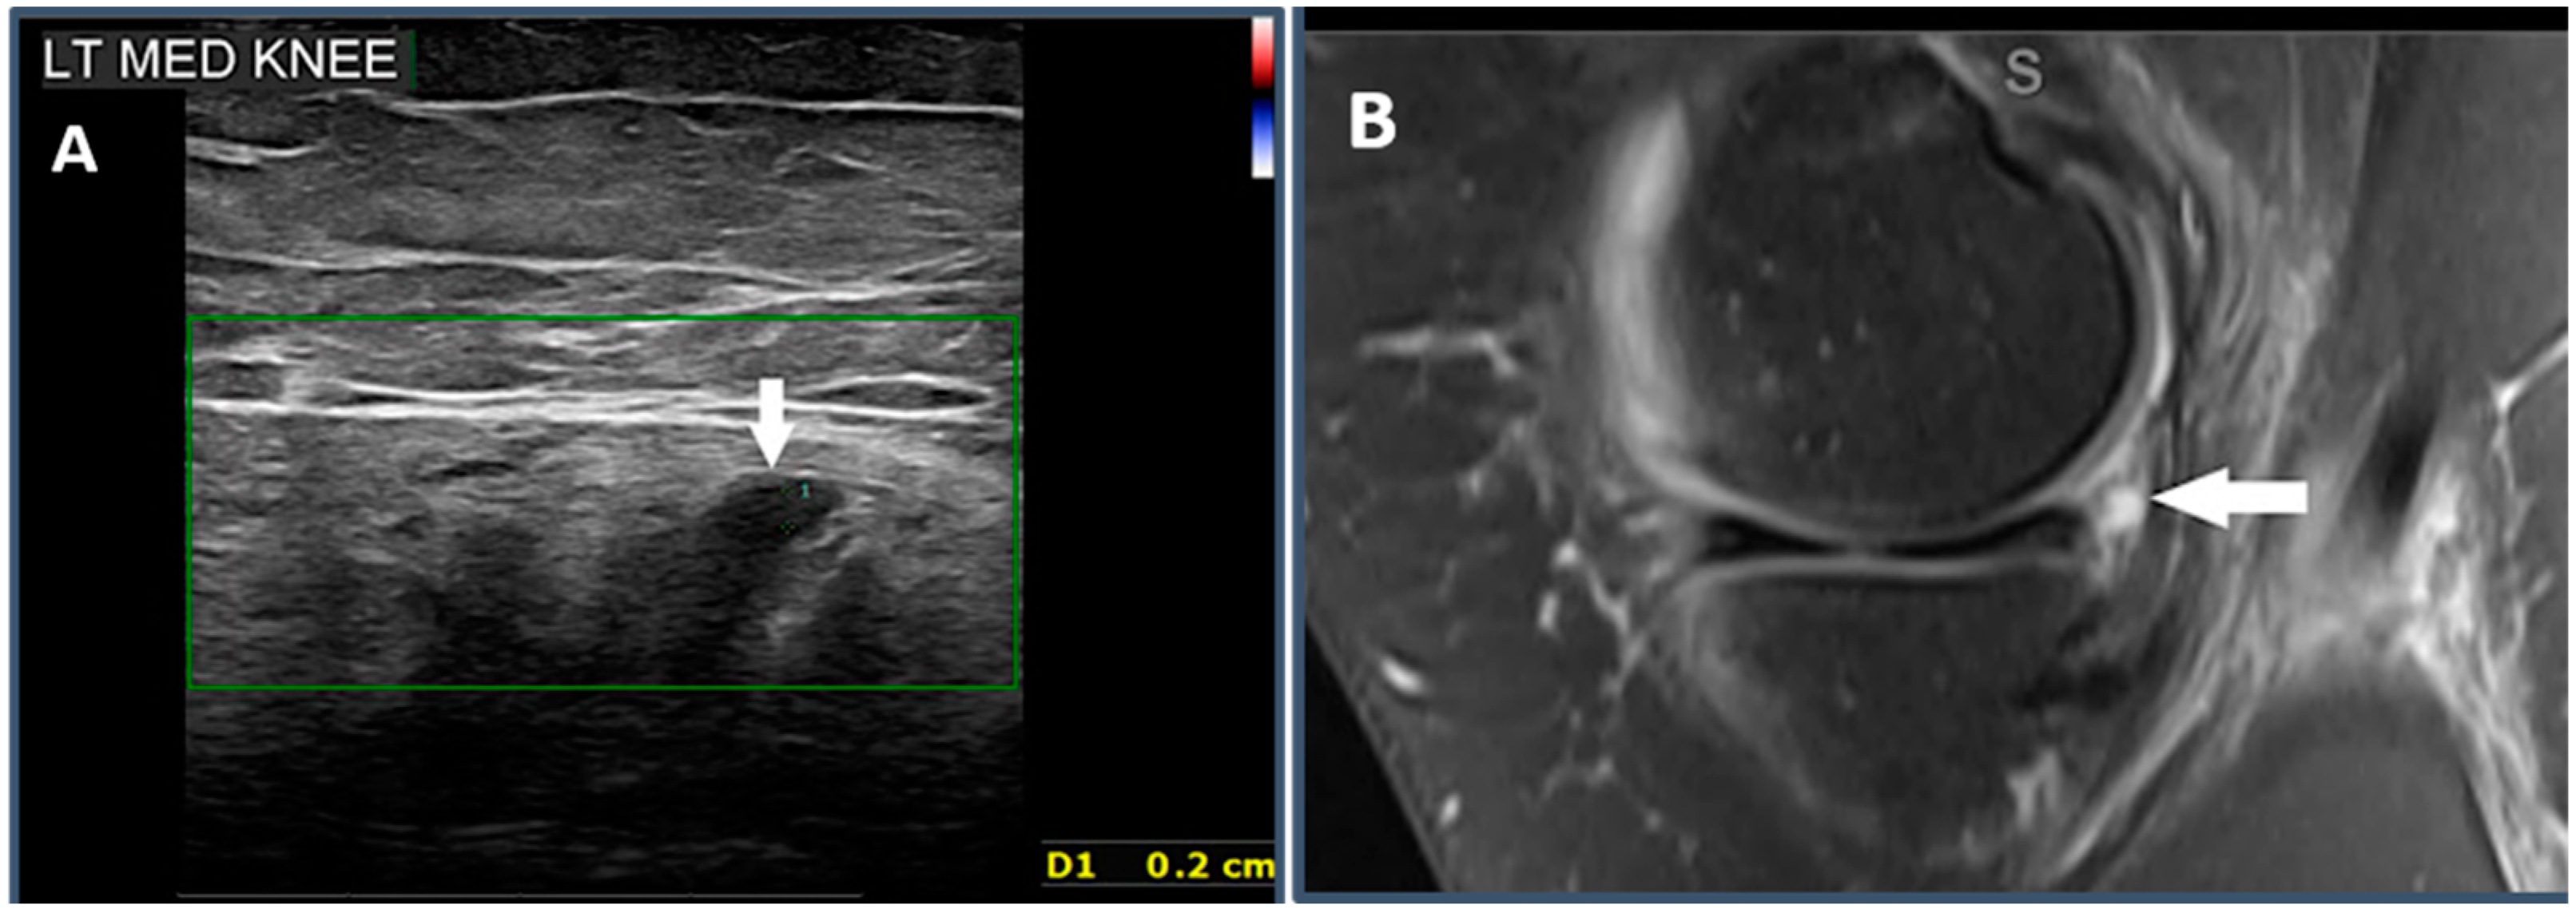

2.5.2. Criterion 2—Parameniscal Cyst